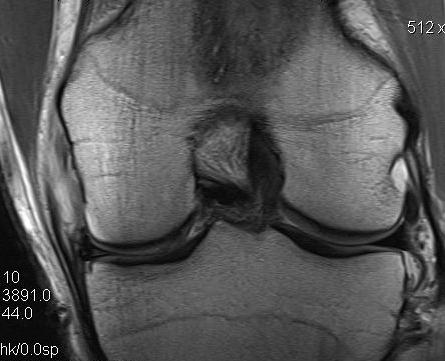

MRI

Classification

Grade I: intact ligament with periligamentous oedema

Grade II: partial tearing with surrounding oedema

Grade III: complete ligament tear

Sites

Femoral avulsion

Midsubstance

Tibial side: wave sign, ensure that the MCL is no flipped above pes anserinus as will not heal (analogous to Stener lesion)

Acute femoral avulsion

Midsubstance MCL tears

Wave sign indicative of tibial avulsion, with ligament retracted above pes anserinus / hamstring tendons

In the chronic setting see thickening of the MCL